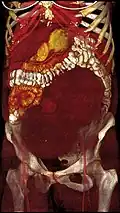

Giant leiomyomas almost filling the abdomen -